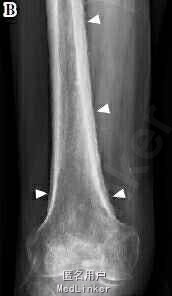

胸部CT提示左肺巨大肿物(图A),痰液细胞学检查示腺癌阳性。另外,患者诉双下肢疼痛,X线检查显示右股骨可见骨膜反应(图B)。骨闪烁显像示双侧股骨及胫骨弥漫皮质摄取(图C),符合肺性肥大性骨关节病(HPOA)。

HPOA是一种通常与肺癌相关的副癌综合征,特点为杵状指、关节炎、肢体疼痛及长骨骨膜炎。其中骨膜炎是HPOA的特征性表现,X线检查常可见对称性骨膜反应,受累部位多见于长骨的双侧干骺端和骨干,这与骨转移有所不同。 DOI: 10.2169/internalmedicine.53.3271。